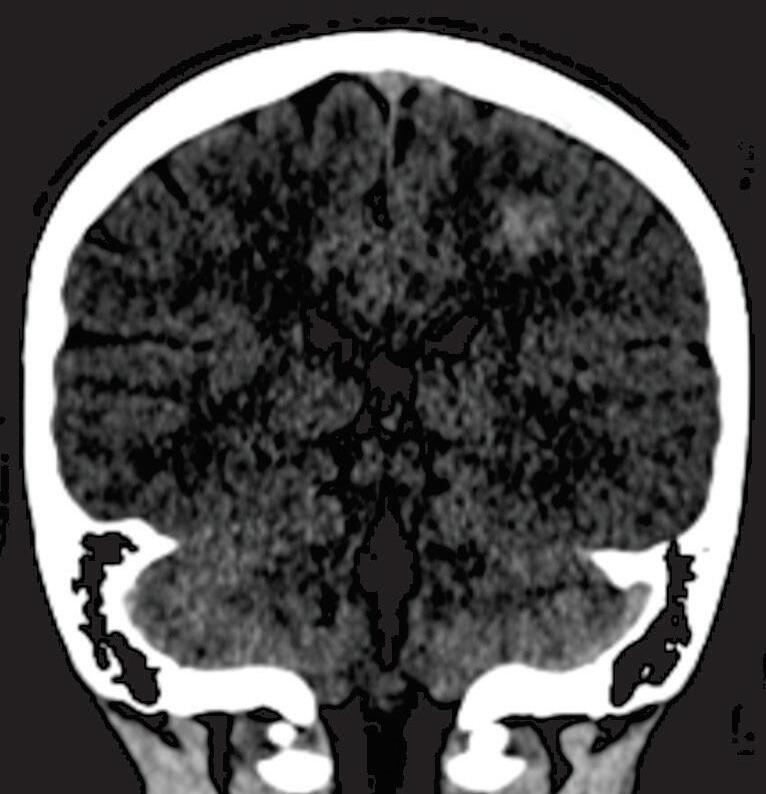

A suspeita diagnóstica das MAVs geralmente é feita por meio de métodos não invasivos de aquisição de imagem, tais como tomografia computadorizada (TC), angiotomografia, ressonância magnética (RNM) e angiorressonância, contudo, as informações anatômicas vasculares necessárias para o planejamento e a execução terapêutica demandam geralmente do estudo dinâmico da angioarquitetura da MAV pela arteriografia cerebral, considerado o exame padrão-ouro para o diagnóstico (Figs. 1-21 e 1-22).35

Em virtude de as manifestações clínicas não serem exclusivas das MAVs, a tomografia computadorizada do crânio sem contraste

é geralmente o primeiro exame realizado na investigação diagnóstica. Algumas alterações presentes nessa tomografia, associadas à história clínica do paciente podem direcionar a suspeição diagnóstica; são eles: pacientes jovens com hemorragia intraparenquimatosa lobar espontânea, sangramento inexplicável intraventricular ou subaracnóideo, presença de calcificações curvilíneas ou salpicadas, ou imagens serpiginosas espontaneamente hiperdensas, que podem corresponder a vasos anômalos integrantes do nidus, a veias de drenagem ou a artérias nutridoras dilatadas. Embora a angiotomografia possibilite uma melhor visualização das estruturas vasculares, a ressonância magnética em contrapartida, permite melhor

Fig. 1-21. TC de crânio sem contraste em cortes (a) axial e (b) coronal. (c) RNM encéfalo T1 com contraste axial. (d) Angiorressonância arterial sagital. Arteriografia digital em (e) AP e (f) perfil, demonstrando MAV não rota localizada no giro pré-central à esquerda nutrida por ramos da artéria cerebral média e caloso marginal esquerdo. Setas azuis apontando para o nidus da MAV.